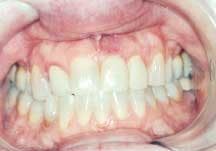

The patient was a 40-year-old female with a moderately high smile line (Figure 1). She presented with a mobile left central incisor that was also discolored and misshapen. Crowns placed years earlier on Teeth Nos. 7 and 10 were also unesthetic, and Teeth Nos. 6, 8, and 11 were malpositioned and discolored as a result of tetracycline therapy that the patient had received as a child. The patient wanted to know the options not only for treating Tooth No. 9, but also for improving her overall smile.